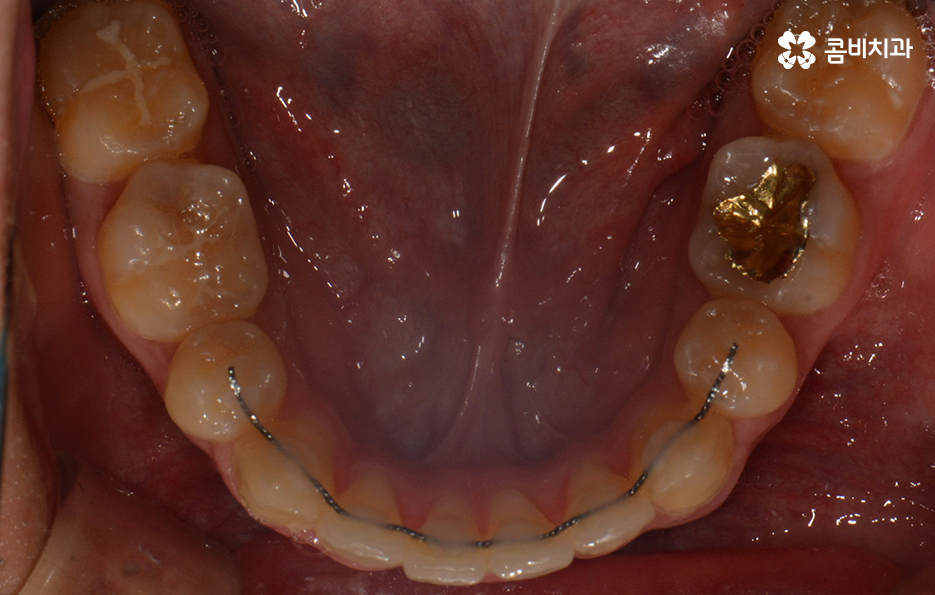

참고로 이번 포스팅에 소개해드린 환자분의 경우

검진부터 발치, 클리피씨 교정을 통해 교정이

마무리 되기 까지 약 2년 정도가 걸렸으며

치료 기간은 개인에 따라 상이하며 정확한 검진 후에

치료 계획에 따라 달라질 수 있어요.

위 환자분의 케이스는 아랫니에 치아 2개를 발치하여

치아의 이동 공간을 확보하였고 발치교정이 진행될 때는

윗니와 아랫니 각각 2개씩 발치를 하는 경우가 많지만

위 사례는 치열, 교합 등을 고려할 때 아랫니 2개만

발치가 진행되었던 경우라고 볼 수 있어요.

왼쪽이 윗니이고 오른쪽이 아랫니인데 치열의 불규칙함이

심한 편이다 보니 평소 음식물이나 치석이 끼기 쉬운 환경이

되고 이러한 구강 환경이 지속된다면 충치와 잇몸질환의 발생률이 높아질 수 있어요.